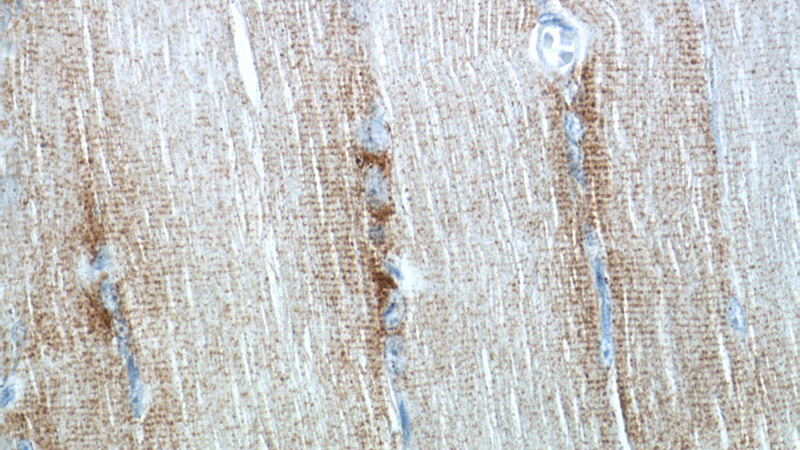

Immunohistochemistry of paraffin-embedded human skeletal muscle tissue slide using Catalog No:109331(CKMT2 Antibody) at dilution of 1:50 (under 40x lens)